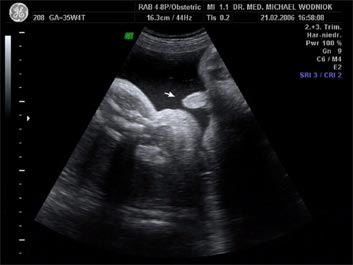

Weitere Ultraschalluntersuchungen sind in der 10./20./30. Schwangerschaftswoche gemäß den Mutterschaftsrichtlinien vorgesehen. Bei erkennbaren Risiken werden  weitere Untersuchungen angeschlossen. Spezielle Ultraschalluntersuchungen zum Ausschluss von kindlichen Entwicklungsstörungen sowie Durchblutungsmessungen der mütterlichen und kindlichen Blutgefäße mittels Farbdopplersonographie gehören zum Leistungsspektrum der Praxis. Auf Wunsch können auch 3D und 4D Untersuchungen angeboten werden.

Sofern sich in dem 2. Ultraschall-Screening um die 20. SSW Hinweise für eine kindliche Fehlbildung ergeben oder anamnestische Risiken für ein generelles, erhöhtes Risiko für eine Fehlbildung vorliegen, können wir in unserer Praxis eine differenzierte, erweiterte Ultraschalluntersuchung im Sinne einer Feindiagnostik der kindlichen Organe durchführen. Diese Untersuchung ist dann in der 22. SSW optimal. Dabei wird auf Hinweiszeichen geachtet, welche eine kindliche Entwicklungsstörung anzeigen können. Es besteht eine enge Kooperation mit den Zentren für pränatale Diagnostik, um im Verdachtsfall die Diagnostik erweitern zu können.